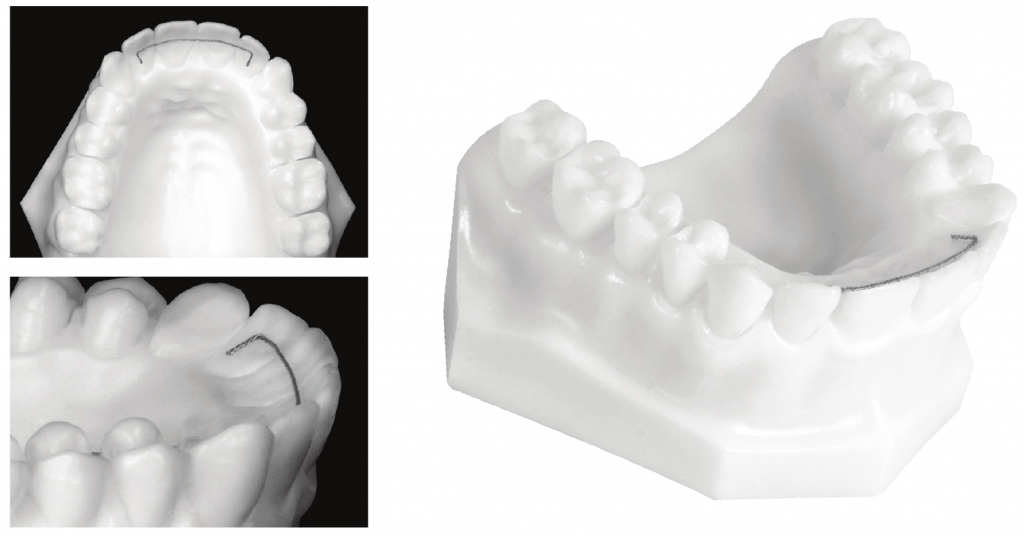

Lower lingual arch – wire adapted to the lingual aspect of lower teeth. U loops allow for adjustments. Can be used for anchorage.

A tooth that has been orthodontically moved will exhibit a tendency to move back towards its pretreatment position due to the elastic supracrestal gingival fibers (free gingival and transseptal collagen fibers). Lower anterior teeth appear to be the most prone to relapse. Occlusal and soft tissue forces may also contribute. Long term retention (e.g. lingual bar) is often used to hold anterior teeth in place to avoid relapse.

After orthodontic treatment, stabilization should last until the lamina dura and PDL reorganize. This could take 2 months for simple movement, or 6 months for more complicated treatment like uprighting, osseous surgery, grafts etc. Full time retention is usually applied for 3-4 months, part time retention for up to 12 months. Permanent retention may be necessary if the teeth are left in an unstable position (e.g. lower incisors, late mandibular growth). Retention is generally not necessary after anterior crossbite treatment (the bite is the retainer). There are a few types of retainers used:

- Fixed retainers – are the most commonly used, often bonded canine to canine. Fixed retainers can be placed lingually or palatally, though care must be taken not to interfere with the patient’s bite. They do not rely on patient compliance, but can break.

- Removable retainer – wire and acrylic base (Wrap around or Standard Hawley) or vacuum formed/3D printed (Essix, Invisalign retainer).